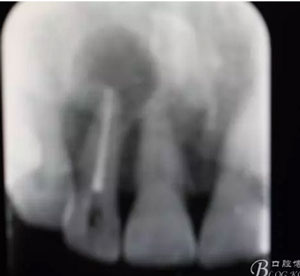

圖2. 12牙齒在我院進行熱牙膠根管充填+樹脂充填。

圖21.術(shù)后的x根尖片影像情況。12根尖區(qū)MTA充填完好。